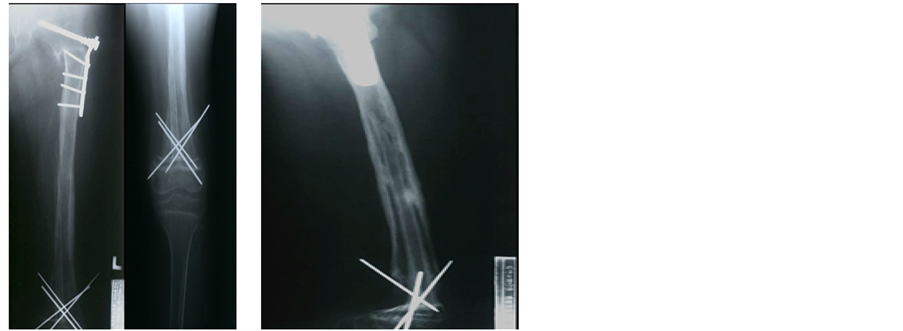

Case 2: (Figures 2(a)-(f)) A 10-year-old girl. Osteogenic sarcoma on left femur (A case of autoclaved autograft and LFG simultaneously, but skip metastasis and allograft later).

Severe painful swelling on whole femur was noted for 6 months. X-ray and MRI show an extensive osteoblastic osteogenic sarcoma (Figure 2(a) and Figure 2(b)).

After confirmed biopsy, combined chemotherapy with high dose of methotrexate and adriamycin for 10 weeks was given. And then, recycled autograft of affected whole femur by autoclaving and LFG into the medullary canal of replaced autoclaved femur was performed simultaneously (Figure 2(c)), and another 12 weeks of hip spicacast immobilization and neo-adjuvant chemotherapy were also given.

The distal epiphysis of affected femur was preserved for her growing. The surgical wound and her general conditions were good.

But one year after, an unusual skip metastasis, may be surgically contaminated, was found on recycled femur by autoclaving (Figure 2(d)), but no lung or other metastasis. Immediately, whole affected femur was excised and replaced with allograft, fixed it with plates (Figure 2(e)).

Six months later, the delayed union was treated with autogenous cancellous chip bone grafts from ilium. One year after, solid bony union, and 4 cm limb shortening was obtained. But four years later, the end result was poor with lung metastasis, and she died (Table 1).

Figure 2. A 10-year-old girl. Osteogenic sarcoma on left femur (A case of autoclaved autograft and LFG simultaneously, but skip metastasis and allograft later). (a) An osteogenic osteosarcoma involving whole femur; (b) An extensive soft tissue invasion on MRI, but no metastatic lesions; (c) After 10 weeks of combined chemotherapy, the affected femur was excised and recycled by autoclaving, getting back at same place combined with LFG; (d) One year later, an unusual skip metastasis was found on recycled femur, but no lung or other metastatic lesions; (e) Whole femur was excised again, replaced with allograft with shortening, and 6 months later, autogenous iliac chip bone graft was done on proximal femur; (f) One year later, solid bone union with 4 cm limb shortening was obtained, but 4 years later, the lung metastasis was found. The end result was poor.